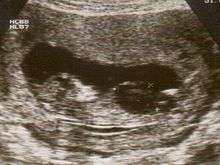

Fetal megacystis is diagnosed during pregnancy by ultrasound imaging procedures. Since it can be associated with genetic abnormalities, further ultrasounds and tests may be administered during pregnancy. It may also be diagnosed as megalocystis, and/or termed megabladder, which is the same condition.